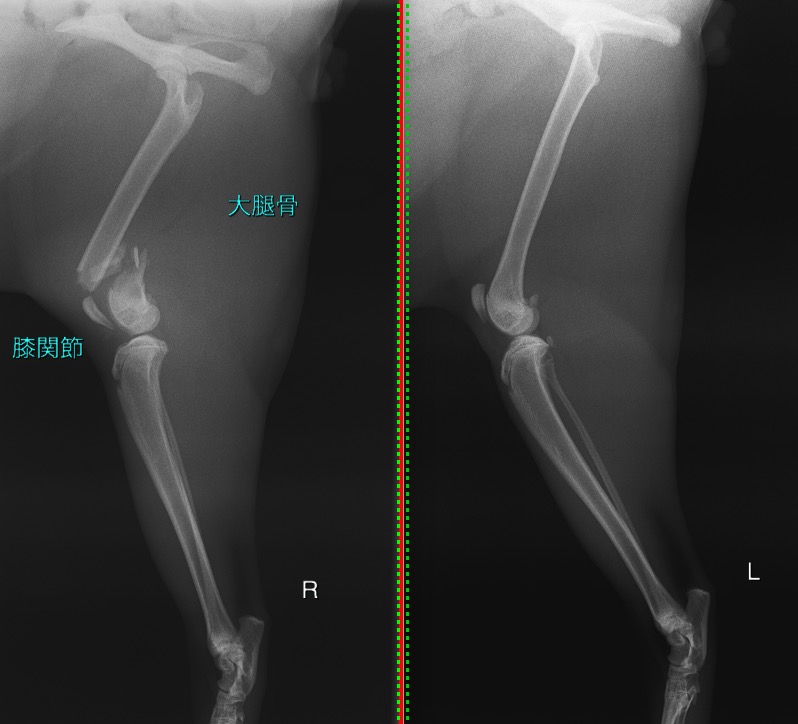

右の大腿骨(太ももの骨)の遠位(膝の関節に近い部分)が粉砕骨折(骨片が3つ以上に砕けてしまう骨折)してしまっていました。

正常肢と比べると、膝の関節に近い部分の骨が折れてしまっているのが分かります。

骨折の見られる右後肢/正常な左後肢